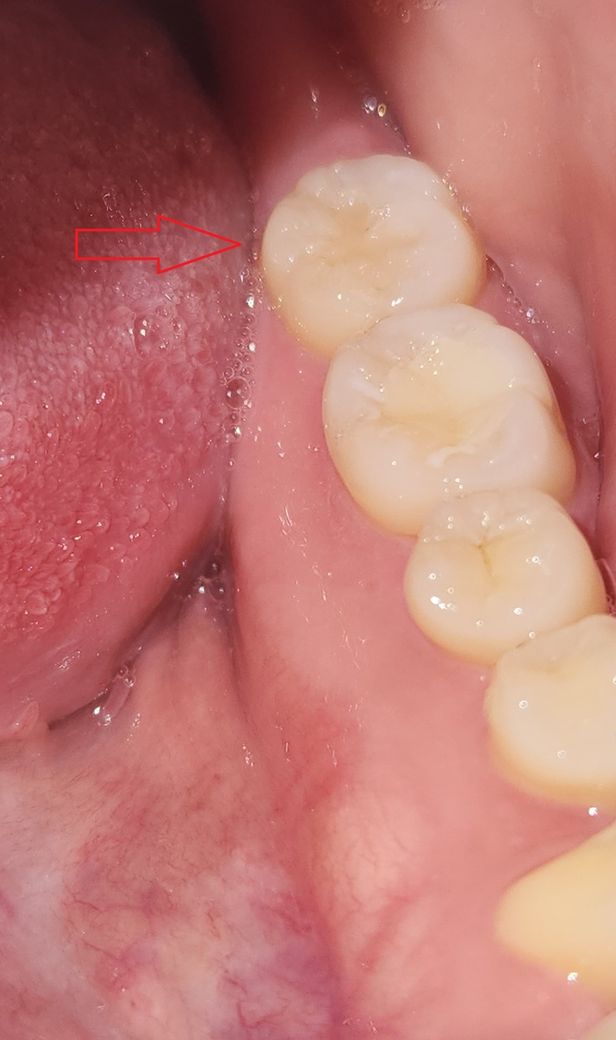

교합면에 약간 선? 크랙같은게 생겨서 그런건지(사진에는 잘안보이지만 선이 있어요)

사진상 충치가 꽤 컸던게 아닌가 싶습니다

사진상으로는 크랙이나 2차충치는 보이진 않습니다. 충치가 깊어서 그럴 수도, 접착과정에서 문제가 있을 수도 있고 자극에 의한 통증이 오래 가는 것일수도 있습니다. 증상이 계속있다면 재치료를 해야할 수 있습니다.

시진상으로 크랙이 보이지는 않으나, 현재 레진 치료 부위의 통증이 지속되는 경우에는 치과 진료를 받고 상태를 정확히 확인해 보길 권합니다. 만약 충치가 추가로 발생시에는 다시 충치를 제거하고, 레진을 씌우는 재치료가 필요로 됩니다.